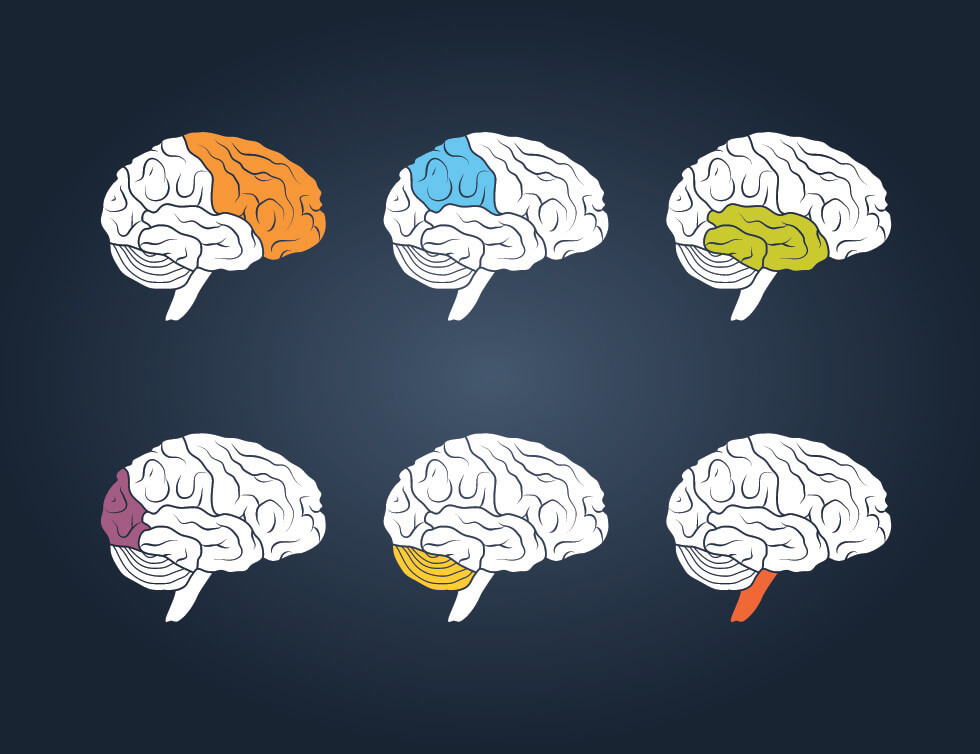

What Is Temporal Lobe

What Is Temporal Lobe

More picture related to What Is Temporal Lobe